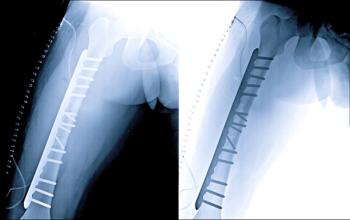

Patients taking nitrogen-containing bisphosphonates have a lower risk of developing and dying from pneumonia after hip fracture compared with patients taking other types of medication for osteoporosis or no drugs for osteoporosis at all, a study published in the Journal of Bone and Mineral Research has found.